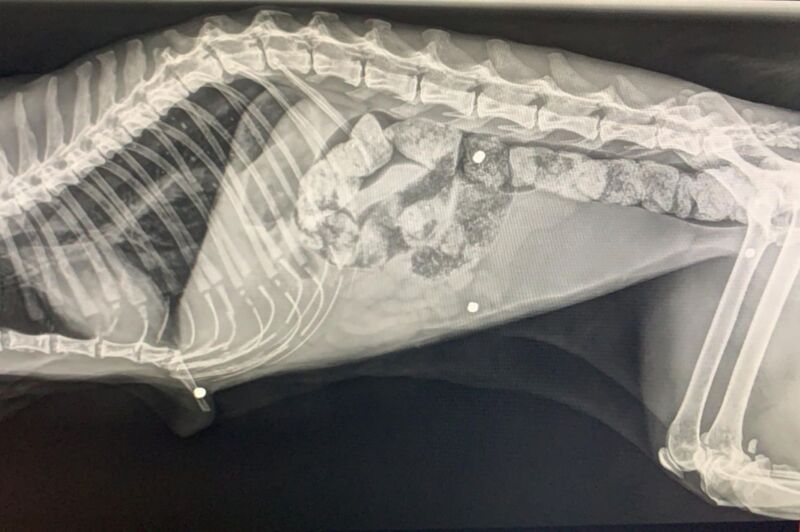

Am Montag, 23. November, wurde ein circa 15 Jahre alter, blinder Kater ins Tierheim gebracht. Den Findern zufolge lag er in einem Straßengraben in Rohrbach (Bezirk Rohrbach). Die tierärztliche Erstuntersuchung und Röntgenbilder zeigen, dass sein ganzer Körper von Schrotkugeln regelrecht durchsiebt ist, zudem hat er ein gebrochenes Brustbein. Getauft wurde der alte Herr auf den Namen „Tizian“. Tierheimleiterin Doris Hofner-Foltin: „Tizian hatte großen Appetit und legte sich sofort ins weiche Bett, nachdem er gegessen hatte. Er ist sehr erschöpft, nicht gechippt, aber kastriert und in einem gesundheitlich sehr schlechten Zustand. Den Verletzungen nach zu urteilen, wurde er mit einer Jagdflinte beschossen. Die vergangene Nacht hat Tizian überstanden, obwohl es extrem kritisch aussah.“

Schrotkugeln können nicht mehr entfernt werden

Die Schrotkugeln befinden sich schon länger in seinem Körper und können nicht mehr entfernt werden. Derzeit bekommt er Injektionen zur Stabilisierung seines Kreislaufes. Das Ehepaar Hofner-Foltin tut sein Möglichstes um Tizian einen angenehmen Lebensabend zu bereiten.